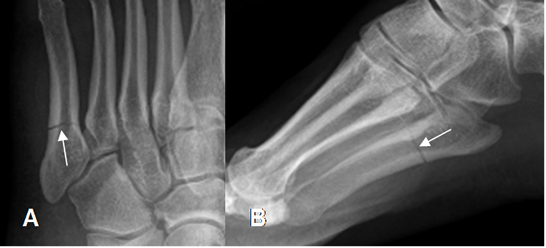

Fig 50 A. Fractura del 5º metatarsiano.

A: Rx oblicua y B: Rx lateral. Fractura transversa, lineal y no desplazada, en el tercio proximal del 5º metatarsiano.